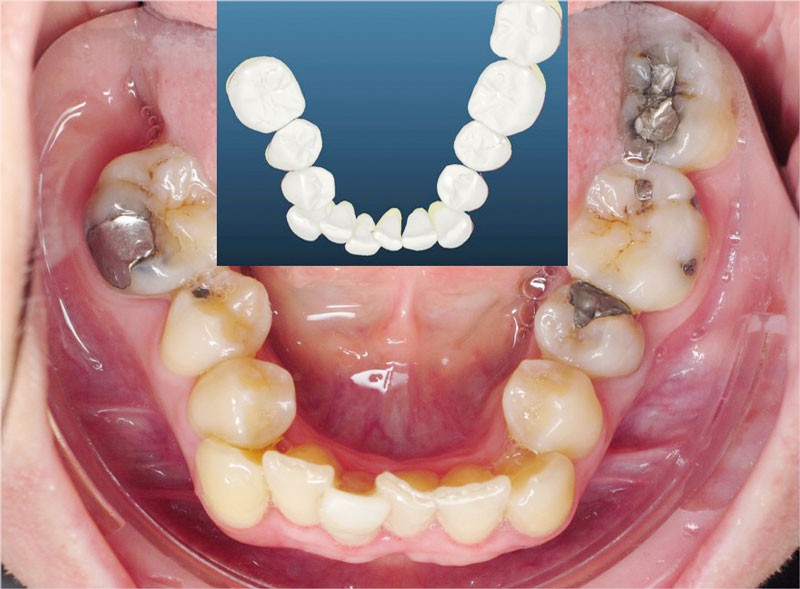

Cas n° 2

Nous lui avons donc proposé un traitement d’alignement avec maintien des 14 et 24 en position de 13 et 23 et optimisation du torque pour favoriser un développement des arcades et chercher à améliorer le sourire et le soutien labial.

La patiente donne son accord pour un appareillage Damon Insignia métal qui permet une individualisation complète des brackets dans les 3 sens de l’espace.

Le projet thérapeutique

Un appareillage Damon métal a été mis en place, réalisé à partir d’un set up numérique Insignia pour obtenir un contrôle précis des torques et de la forme d’arcade et réduire le temps de finition grâce à un collage indirect très précis.

De larges surélévations postérieures étalées ont été mises en place et la patiente a porté des élastiques précoces suivant les principes de la technique Damon. Les 14 et 24 rempliront le rôle des 13 et 23.

L’objectif, en utilisant la technique Insignia est de réduire le temps de traitement de 28 à 18 mois avec 12 rendez-vous (fig. 5 à 14).